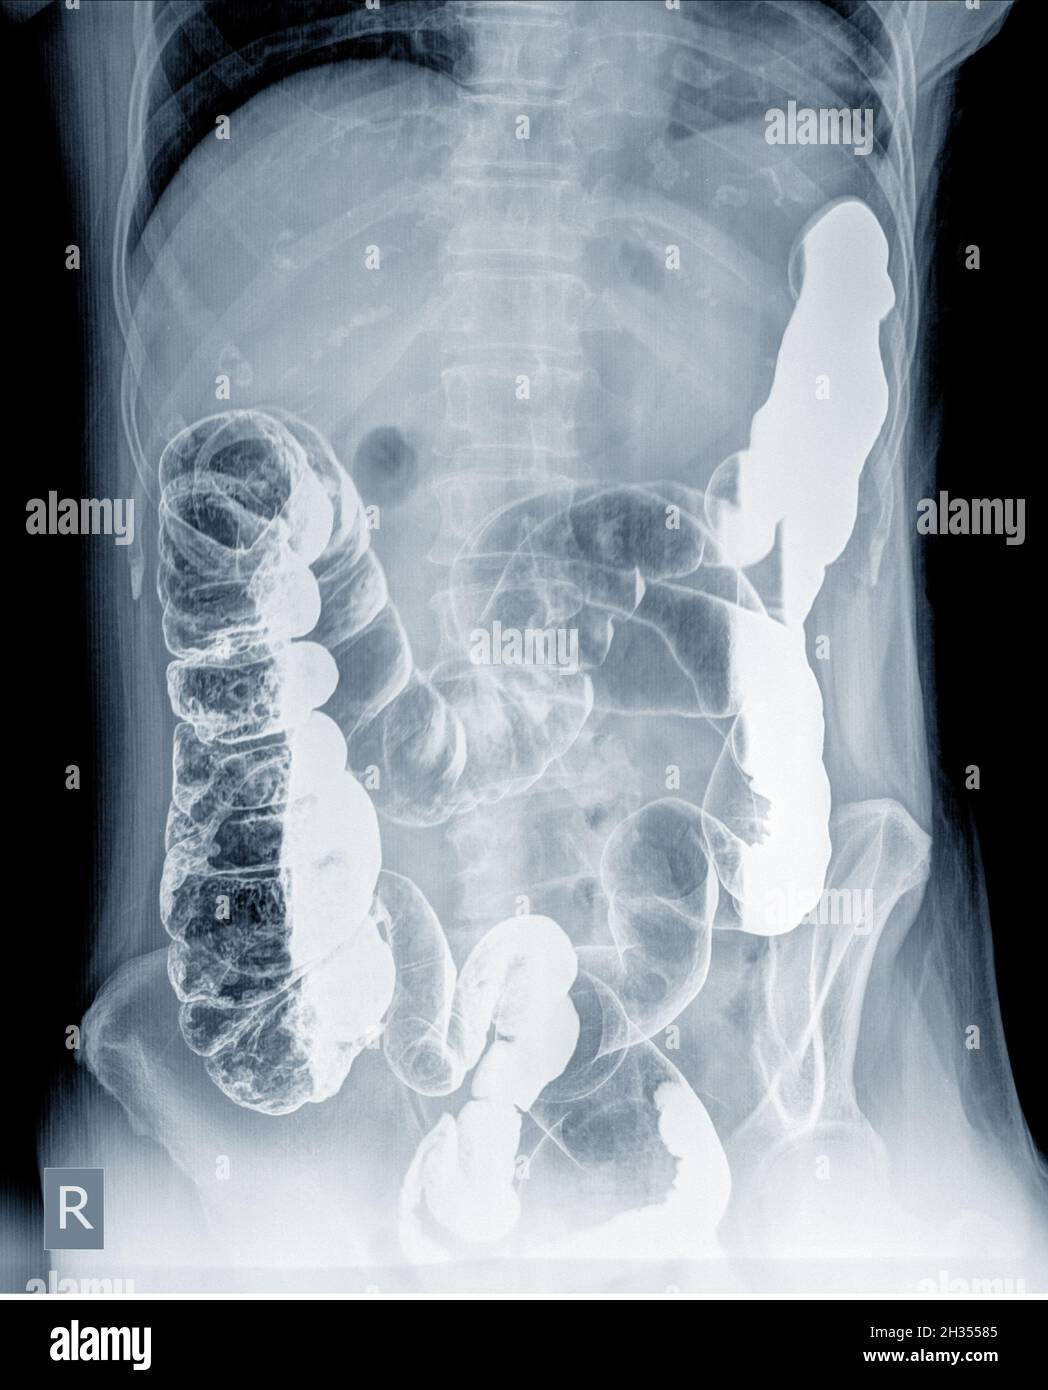

Examen Radiologique à La Recherche D'anomalies Du Côlon Par Lavement La Air Dans Le Colon Cela peut provoquer des ballonnements, des douleurs abdominales et des. Elle est assez fréquente et source d'inconfort abdominal. Nous parlons plus communément de ballonnements. Mais contrairement au phénomène d’aérocolie où les gaz produits en excès s’accumulent dans le côlon, l’air avalé se concentre. L’aérophagie est un trouble digestif caractérisé par une accumulation anormale d’air dans l’estomac. Si une partie de. Air Dans Le Colon.